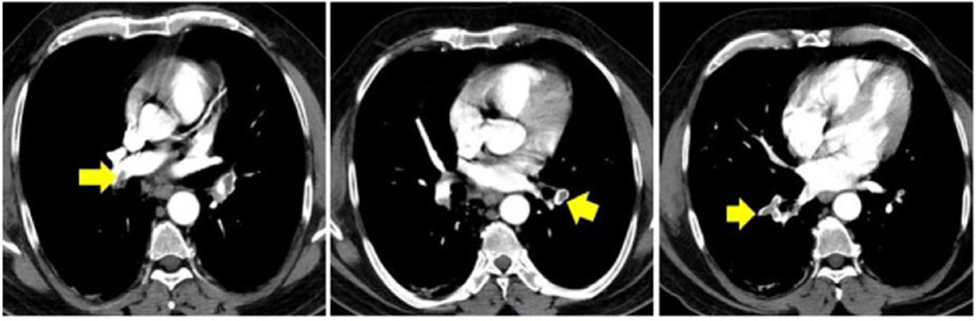

CT ngực của một bệnh nhân với đau ngực và độ bão hòa oxy thấp 8 tuần hậu COVID cho thấy hình ảnh thuyên tắc phổi hai bên